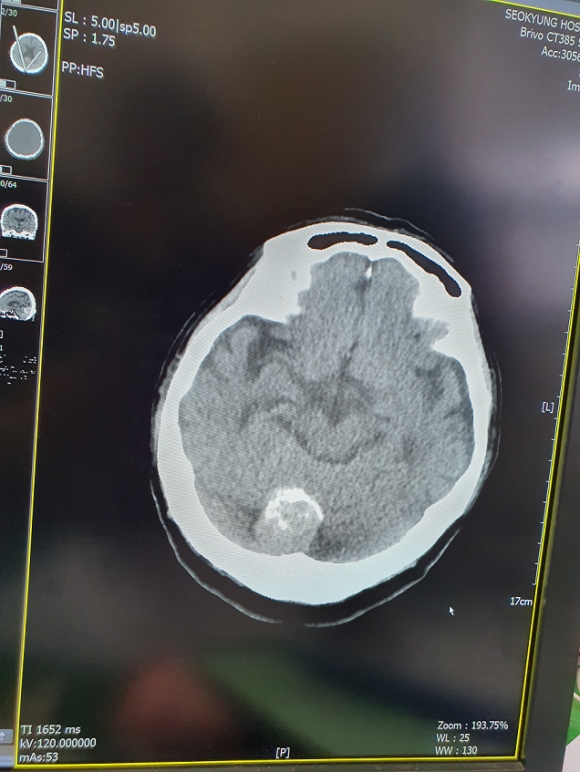

°ÅⱺÀº ÀÇ·áÃë¾à°èÃþÀÎ Àú¼Òµæ ÁÖ¹ÎÀ» ´ë»óÀ¸·Î Áúº´À» Á¶±â¿¡ ¹ß°ßÇϰí Ä¡·áÇÒ ¼ö ÀÖµµ·Ï 2020³â Ãë¾à°èÃþ Áúº´¿¹¹æ°ËÁø(³úÁúȯ¡¤Æ¯¼öÁúº´) »ç¾÷À» ½Ç½ÃÇÑ´Ù°í ¹àÇû´Ù.

³úÁúȯ °ËÁøÀº MRI(³úÁ¶Á÷°Ë»ç), MRA(³úÇ÷°ü°Ë»ç) 2Á¾À¸·Î º»Àκδã±Ý 240,000¿ø À̳» Áö¿øÇϸç, Ư¼öÁúº´ °ËÁø(Àü¸³¼±¾Ï¡¤³¼Ò¾Ï, °©»ó¼±Áúȯ, ½ÉÀåÁúȯ, Ç÷°üÁúȯ, °ñ¹Ðµµ)Àº ³²³à °¢°¢ 5Á¾ º»Àκδã±Ý Àü¾×À» Áö¿øÇÑ´Ù.

°ËÁø´ë»óÀº °Åⱺ¿¡ ÁÖ¼Ò¸¦ µÐ ¸¸ 40¼¼ ÀÌ»ó ÀÇ·á±Þ¿© ¼ö±Þ±ÇÀÚ ¹× °Ç°º¸Çè°¡ÀÔÀÚ º¸Çè·á ±âÁØ ÇÏÀ§ 50%(Á÷Àå : 10¸¸¿ø, Áö¿ª : 9¸¸7000¿ø ÀÌÇÏ) Áß °ËÁø°ú °ü·ÃÇØ Áõ»óÀÌ ÀÖ´Â ÀÚÀ̸ç, Áö³ÇØ °ËÁøÀ» ¹ÞÀº ´ë»óÀÚ´Â Á¦¿ÜµÈ´Ù.

½ÅûÀº ¿À´Â 10ÀϺÎÅÍ ¼±Âø¼øÀ¸·Î ¸ðÁýÇϸç, º¸°Ç¼Ò(Áö¼Ò¡¤Áø·á¼Ò)¸¦ ¹æ¹®ÇØ ½ÅûÇÏ¸é µÈ´Ù.

½Åû ÀοøÀº Ư¼öÁúº´°ËÁø 72¸í, ³úÁúȯ °ËÁø 55¸íÀ¸·Î Çѱ¹°Ç°°ü¸®Çùȸ °æ³²ÁöºÎ, ¼°æº´¿ø Áß Èñ¸ÁÇÏ´Â °÷¿¡¼ °ËÁøÀ» ¹ÞÀ» ¼ö ÀÖ´Ù.

Á¶ÃáÈ º¸°Ç¼ÒÀåÀº ¡°À̹ø Ãë¾à°èÃþ Áúº´¿¹¹æ°ËÁø(³úÁúȯ¡¤Æ¯¼öÁúº´) ±âȸ¸¦ ÅëÇØ ÀÇ·áÃë¾à°èÃþÀÌ Áúº´À» Á¶±â¿¡ ¹ß°ßÇϰí Ä¡·áÇÔÀ¸·Î½á °Ç°ÇÑ »îÀ» ¿µÀ§ÇÒ ¼ö Àֱ⸦ ¹Ù¶õ´Ù¡±°í ¸»Çß´Ù.